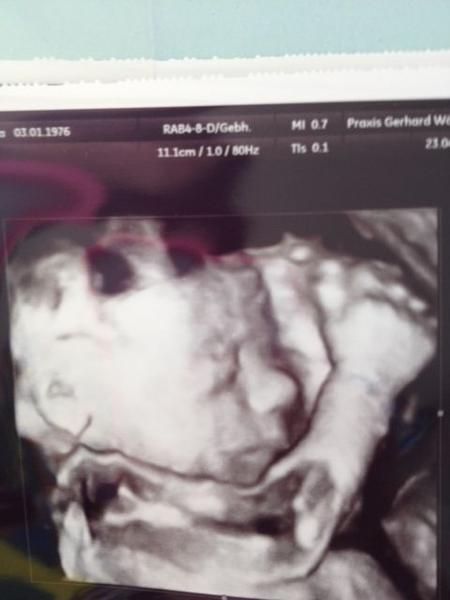

Bin gespannt auf Fotos